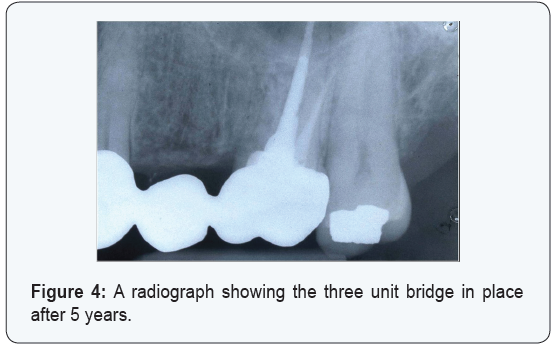

2months later after complete healing of the socket an impression was taken and 3 unit bridge was fabricated and since then the patient has no complaint. Five years later a radiograph was taken and showed no sign of problem (Figure 4).